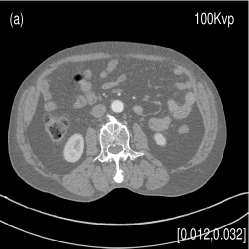

We acquired the Catphan©600 phantom data on a tabletop cone-beam CT (CBCT) system whose geometry matched that of a Varian On-Board Imager (OBI) on the Trilogy radiation therapy machine. We inserted iodine solutions with nominal concentrations of and into the phantom. There were pixels with a physical size of per pixel on the CB4030 flat-panel detector (Varian Medical Systems). The DECT measurements were obtained at kVp and kVp with a tube current of mA and a pulse width of ms. We acquired projections over in each scan. Using a fan-beam geometry with a longitudinal beam width of on the detector niu2010shading , We acquired projections with scatter contamination inherently suppressed. We used a contrast rod slice of the Catphan©600 phantom to evaluated the proposed method. We reconstructed attenuation images of size with a pixel size of . Fig. 3 shows the low- and high-energy CT images. Fig. 3(a) identifies the rods with labels: Teflon (labeled as ), Delrin (labeled as ), Iodine solution of (labeled as ), Polystyrene (labeled as ), low-density Polyethylene (LDPE) (labeled as ), Polymethylpentene (PMP) (labeled as ), Iodine solution of (labeled as ). Fig. 3(b) shows selected basis materials and ROIs in white dashed line circles: Teflon (ROI1), Delrin (ROI2), Iodine solution of (ROI3), PMP (ROI4), Inner soft tissue (ROI5) and Air (ROI6).

We also evaluated the proposed PWLS-TNV- method using clinical pelvis data. The patient’s pelvis data was acquired by Siemens SOMATOM Definition flash CT scanner using DECT imaging protocol. Table 4 lists acquisition parameters in the pelvis data scan. Fig. 5 shows the high- and low-energy CT images of the pelvis data. Fig.5 (b) shows selected basis materials, bone, iodine, muscle, fat and air, and their assosicated ROIs highlightened in white dashed line circles. We implemented the Direct Inversion method in mendonca2014a and used its results as the initialization for the PWLS-EP-LOOP xue2017statistical and the proposed PWLS-TNV- method. Fig. 6 shows the decomposed material images by the Direct Inversion, the PWLS-EP-LOOP and the PWLS-TNV- method. Table 5 summarizes the means and noise STDs of the decomposed material images by the above three methods. The volume fraction (VF) accuracies are , , and for the Direct Inversion method, the PWLS-EP-LOOP method and the proposed PWLS-TNV-, respectively. Compared with the Direct Inversion and PWLS-EP-LOOP method, the proposed method improves the VF accuracy by and respectively. The proposed PWLS-TNV- method decomposes basis material images more accurately, suppresses noise and decreases crosstalk, while retaining spatial resolution of the decomposed images compared to the other two methods.